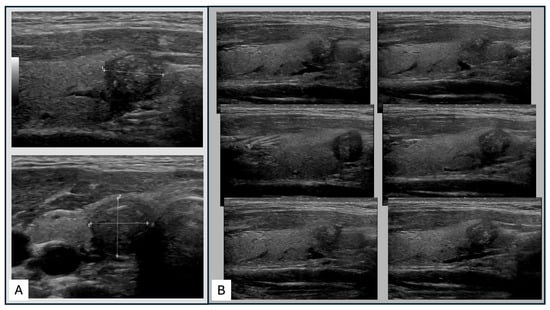

2.4. Thyroid Ultrasound Techniques

- Seifert, P.; Maikowski, I.; Winkens, T.; Kühnel, C.; Gühne, F.; Drescher, R.; Freesmeyer, M. Ultrasound Cine Loop Standard Operating Procedure for Benign Thyroid Diseases-Evaluation of Non-Physician Application. Diagnostics 2021, 11, 67. [Google Scholar] [CrossRef]